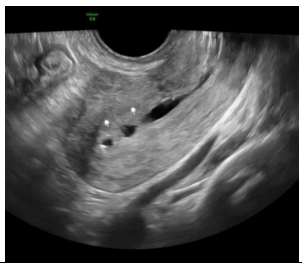

Paciente nulípara, sem uso de contraceptivos, comparece ao ginecologista com queixa de dispareunia e dismenorreia importantes, com piora cíclica no período menstrual. Apresenta a seguinte imagem ao exame de ultrassom endovaginal:

A imagem ecográfica sugere como diagnóstico

Paciente nulípara, sem uso de contraceptivos, comparece ao ginecologista com queixa de dispareunia e dismenorreia importantes, com piora cíclica no período menstrual. Apresenta a seguinte imagem ao exame de ultrassom endovaginal:

A imagem ecográfica sugere como diagnóstico